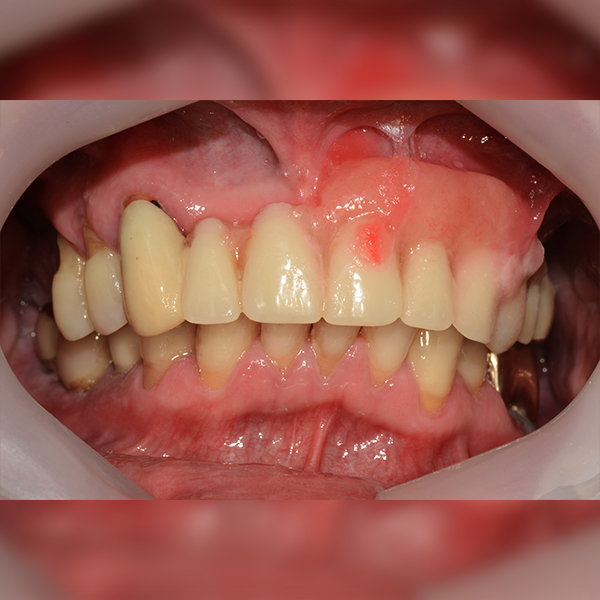

3. Trường hợp 205 Shim*Soo, 60 tuổi 2017-12-12 / 2018-11-22

Trường hợp 205 Shim*Soo, 60 tuổi 2017-12-12 / 2018-11-22